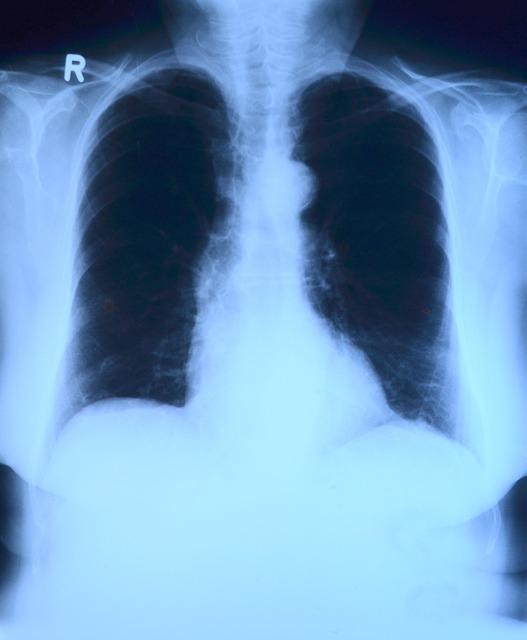

筛查肺癌,CT 不如做胸片?

一提起胸部 CT 或 X 线检查,很多人就会想到辐射!于是经常出现这样的情况,医生检查时发现了可疑的情况,一建议做个胸部 CT,就有人会不解地问:“我又不咳嗽、不胸痛的,做 CT 干啥,还有辐射呢?”

这还真不是医生没事找事,肺癌临床表现多种多样,早期通常没有症状或症状不明显,初诊时 75%的患者已发展为晚期肺癌,早期肺癌只有在胸部 CT 扫描或高危人群筛查时才会被发现。

结论:肺癌高危人群筛查早期肺癌,多个国内外指南均推荐低剂量 CT 平扫为首选。平时体检、诊疗检查时,偶尔做一次 CT,并不会损伤身体。备孕、已孕、哺乳期女性受检者,应在检查前告知医生,孕期女性应避免做 CT 检查。